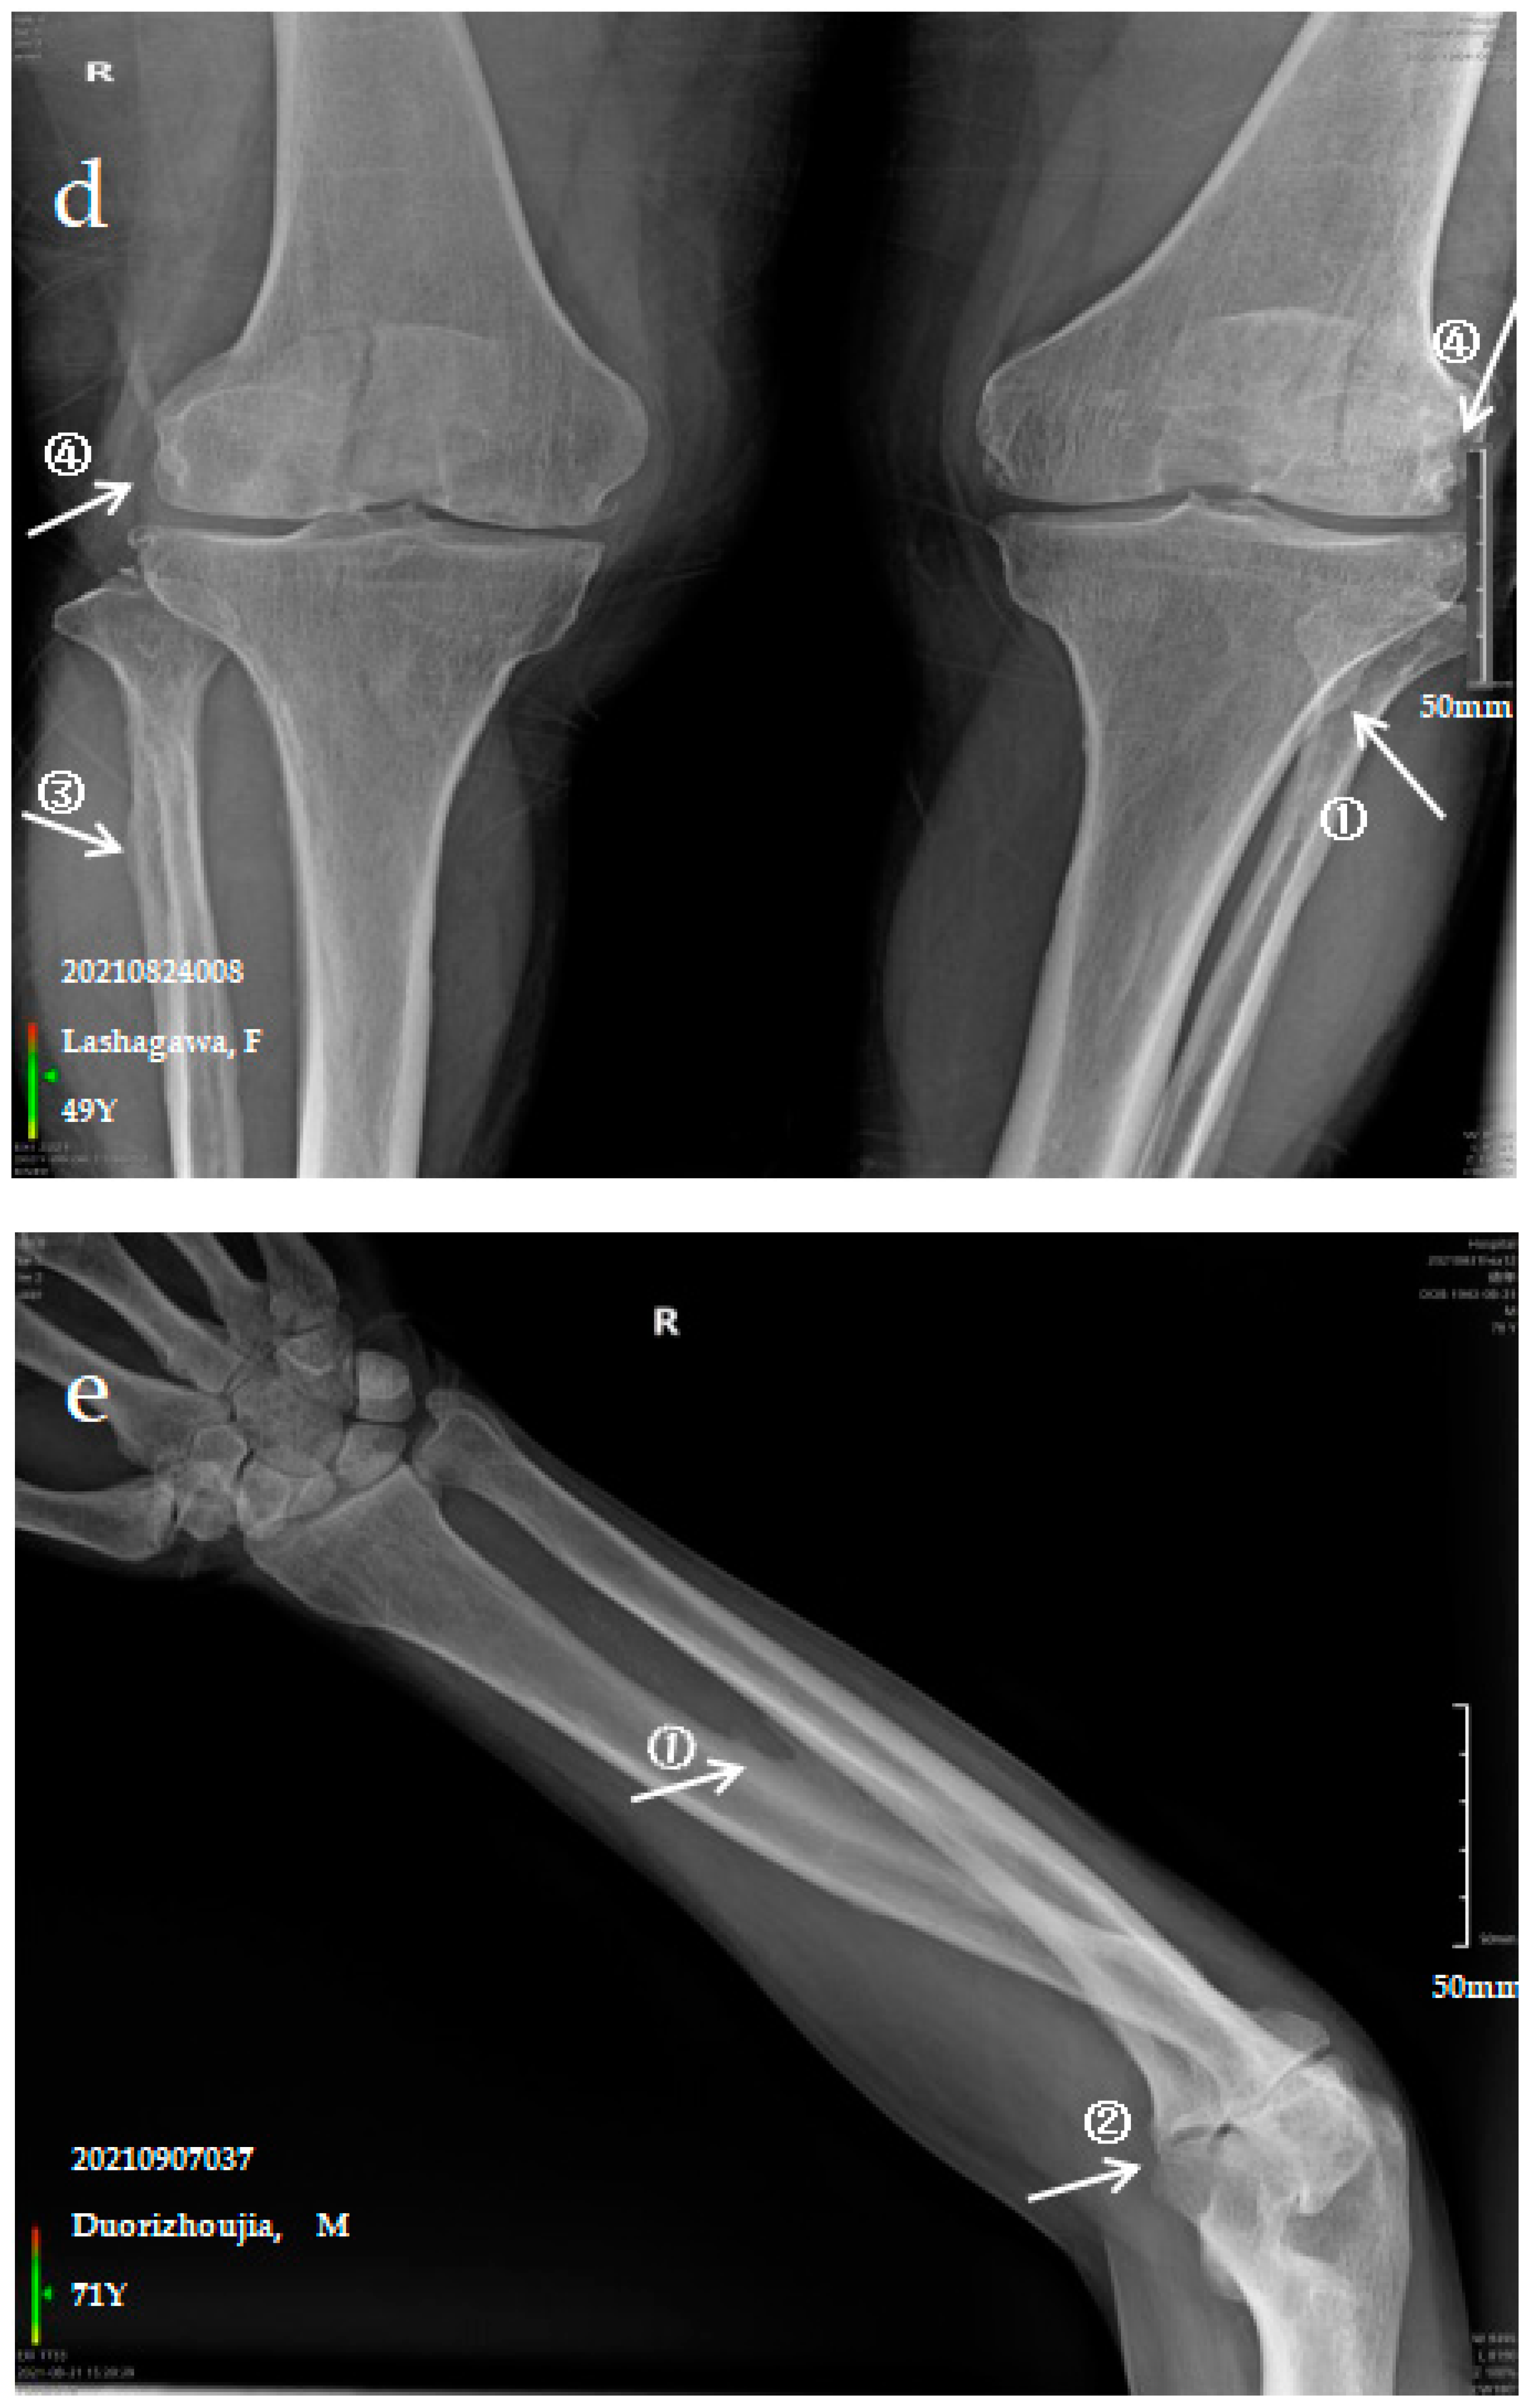

Figure 1.

X-ray imaging of SF patients. The anteroposterior actinogram of the upper limb (a) and both lower limbs (b) of patient with mild SF, the anteroposterior actinogram of the upper limb (c) and both lower limbs (d) of patient with moderate SF, the anteroposterior actinogram of the upper limb (e) and both lower limbs (f) of patient with severe SF. ①: ossification of interosseous membrane; ②: degeneration of the elbow joint; ③: Ossification shadow; ④: Ossification of knee joint capsule; ⑤: ossification of soleus tendon.

3.2.3. Case Analysis of a Patient Diagnosed by X-ray with Severe SF

The patient is a 71-year-old male with severe bone and joint pain, limited activity and no ability to work. The anteroposterior actinogram of the upper limb (Figure 1e) shows obvious ossification of the interosseous membrane of the ulna and radius, forming a large fin-like ossification near the ulna and radius. The pronator teres muscle tendon shows obvious ossification, and a stalactite ossification shadow can be seen in the radial head. There is obvious degeneration of the elbow joint. The anteroposterior actinogram of both lower limbs (Figure 1f) shows ossification of the tibiofibular interosseous membrane, with a colliculus appearance. The peroneus longus tendons show obvious ossification, as do the soleus tendon, knee joint capsule and tibial collateral ligament.

Ossification of the interosseous membrane has a high incidence and specificity in SF and is one of the important diagnostic signs of SF. Ossification of the interosseous membrane was more obvious in patients with severe SF than in those with mild or moderate SF.